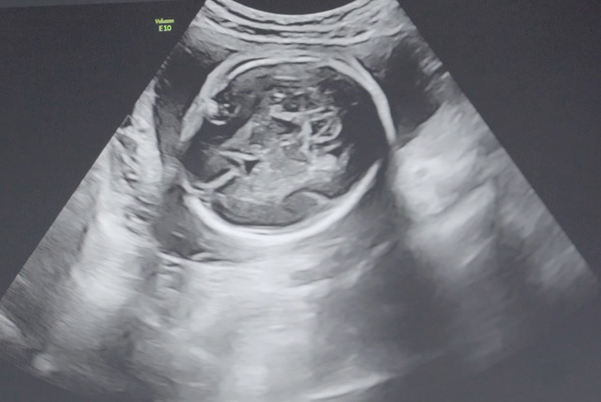

怀孕四个月担心胎停是否需要每周都去医院做b超检查?

问题描述: 我已经怀孕四个月了,怀孕期间,我一直非常关注自己的身体健康,因为听说胎停的时候,孕妇不容易发现,所以总是担心胎儿会出现这种情况,我知道定期去医院进行产检可以提前预防一些意外,所以我就在考虑要不要增加去医院的次数,现在想问问大家,你们觉得我是否需要每周都去一趟医院呢?

胎停指的是胚胎生长发育的某个阶段,停止正常生长直至死亡的现象,有些孕妈在怀孕四个月的时候非常担心自己会出现这种情况,所以想通过频繁去检查B超的形式来预防胎停,实际上,大家不需要每周都去医院做B超,主要原因有下面几点: